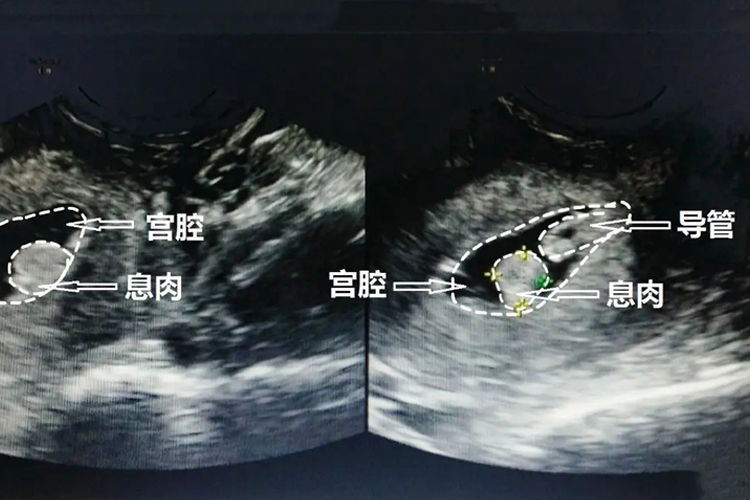

子宫内膜息肉

临床表现:主要为子宫不规则出血或月经过多,在生育期妇女可造成不孕,也有些患者无任何临床症状。

影像表现:子宫增大不明显或略大,宫腔线消失或变形,宫腔内见中-高回声结构,可为多个或单个,大小差别很大,小者数毫米,大者数厘米,常呈团状、水滴状,基底部子宫内膜连续。